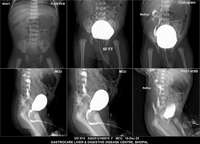

Section: URETHROGRAM

Total: 95 Cases